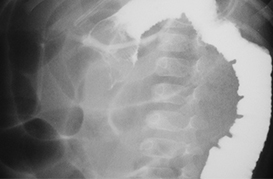

Enfermedad de Hirschsprung

Invaginación Intestinal